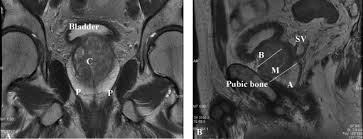

Strictly sagittal to the body axis. Prostate mri has become an increasingly frequent examination faced in daily radiological practice and is usually acquired as either multiparametric or biparametric mri of the prostate. The coronal view is from the top, showing the left and right sides of the gland.

Anatomical changes during physiological voiding in men. The probe is angled from one side. The important role of magnetic resonance imaging (mri) in the anatomic evaluation, detection, and staging of prostate cancer is well established. Axial t1wi of pelvis 2.